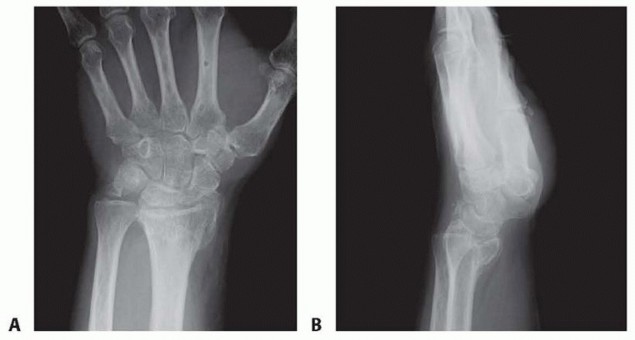

TECH FIG 2 • A,B. AP and lateral radiographs showing a circular plate fusion construct. On the lateral view, the plate is nicely seated to prevent dorsal impingement.